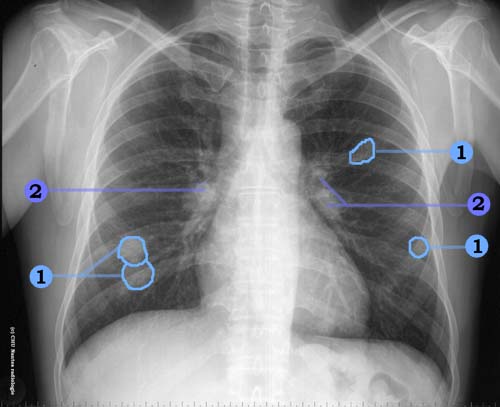

Lésions nodulaires

1 . opacités nodulaires hilaires : adénopathies

2 . opacités nodulaires solides bilatérales à contours nets en lâcher de ballons